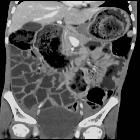

They are known to cause small bowel obstruction and sometimes CT may demonstrate the bezoar as a mass in the obstructed segment of bowel. The bezoar may be outlined by fluid in the proximally dilated small bowel, and the mass may be mottled owing to air trapped within it.